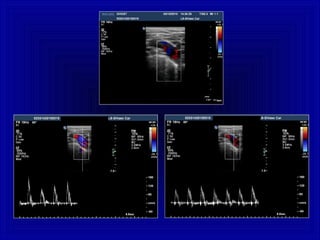

Segnale Arterioso

flusso ad “alta resistenza”

• arterie periferiche

• carotide esterna

• alcuni flussi

“tumorali”

basso flusso diastolico

flusso a “bassa resistenza”

• arterie cerebrali

• arterie renali

• arterie parenchimali

• flogosi (iperemia)

flusso diastolico elevato

• flusso continuo, senza escursione sisto -

diastolica, di bassa velocità, modulato dal

respiro

Analisi Qualitativa

Segnale Venoso